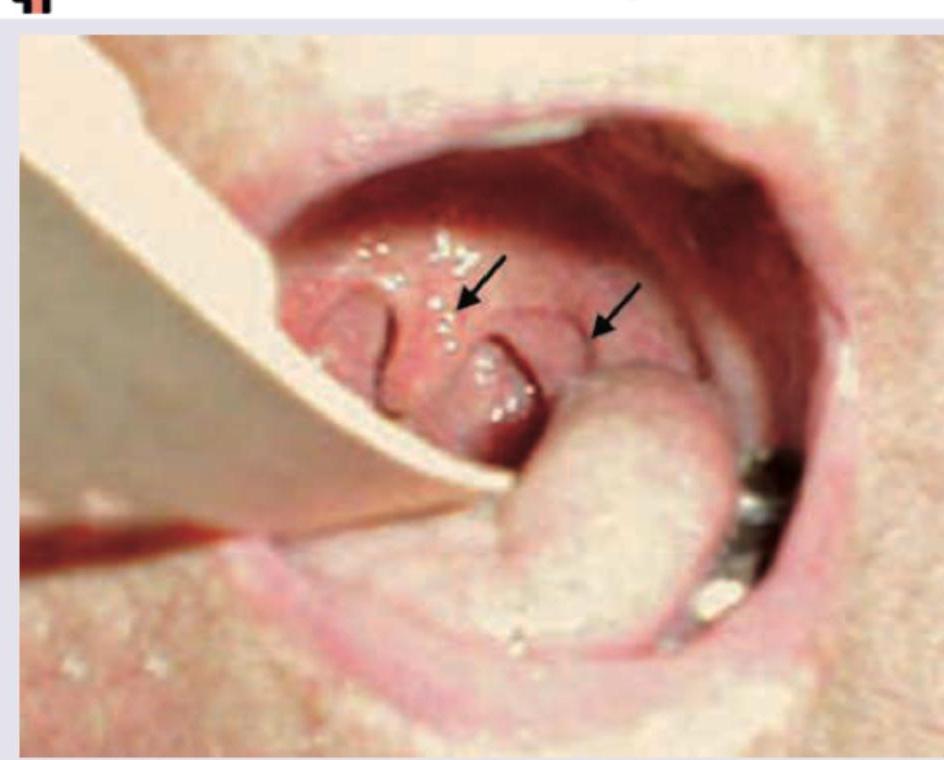

A 3-year-old child presents with fever, unilateral throat pain and trismus. Throat examination shows:

Explanation: ***Peritonsillar abscess*** - The image shows a **unilateral bulge** of the soft palate and displacement of the **uvula**, consistent with a peritonsillar abscess. - Clinical features of **fever, unilateral throat pain, and trismus** are classic symptoms of a peritonsillar abscess. *Ludwig's angina* - This is a **bilateral cellulitis of the submandibular and sublingual spaces**, typically presenting with **swelling of the floor of the mouth** and elevation of the tongue. - It does not primarily present with unilateral throat bulging or uvula deviation as depicted. *Retropharyngeal abscess* - An abscess in the **retropharyngeal space** would cause a bulge in the posterior pharyngeal wall, which is not shown in the image. - While it can cause fever and difficulty swallowing, **trismus** and a visible pharyngeal bulge as shown are less typical. *Parapharyngeal abscess* - A parapharyngeal abscess is located laterally to the pharynx and typically presents with **external neck swelling**, fever, and possibly trismus. - It would not cause the **uvula deviation** and **bulging of the soft palate** seen in the image within the oral cavity.

Explanation: ***Quinsy (Peritonsillar abscess)*** - **Quinsy** is a **peritonsillar abscess** that presents with fever, severe throat pain, and the pathognomonic sign of **unilateral tonsil pushed toward the midline**. - The abscess forms in the **peritonsillar space** (between the tonsillar capsule and superior constrictor muscle), causing **medial displacement of the tonsil** and **bulging of the soft palate**. - Patients typically have **trismus, dysphagia, "hot potato voice"** and may have visible neck swelling. - This clinical presentation exactly matches the description: tonsil pushed to midline is the **classic finding for peritonsillar abscess**. *Parapharyngeal abscess* - A **parapharyngeal abscess** involves the deep parapharyngeal space lateral to the pharynx. - While it can cause neck swelling and fever, it typically causes **fullness and induration of the lateral pharyngeal wall** rather than prominent medial displacement of the tonsil itself. - The **tonsil is usually NOT pushed to the midline** in parapharyngeal abscess; instead, there is lateral pharyngeal wall bulging. - Often presents with more prominent external neck swelling below the angle of mandible. *Retropharyngeal abscess* - A **retropharyngeal abscess** occurs in the retropharyngeal space behind the posterior pharyngeal wall. - Presents with **posterior pharyngeal wall bulge**, neck stiffness, and dysphagia. - Does **NOT cause medial displacement of the tonsil** as the abscess is posterior, not lateral to the tonsil. *Tonsillitis* - **Acute tonsillitis** causes bilateral tonsillar inflammation with erythema and exudates. - While both tonsils may be enlarged, there is **no unilateral medial displacement** of one tonsil. - Less likely to cause significant neck swelling compared to deep space infections.